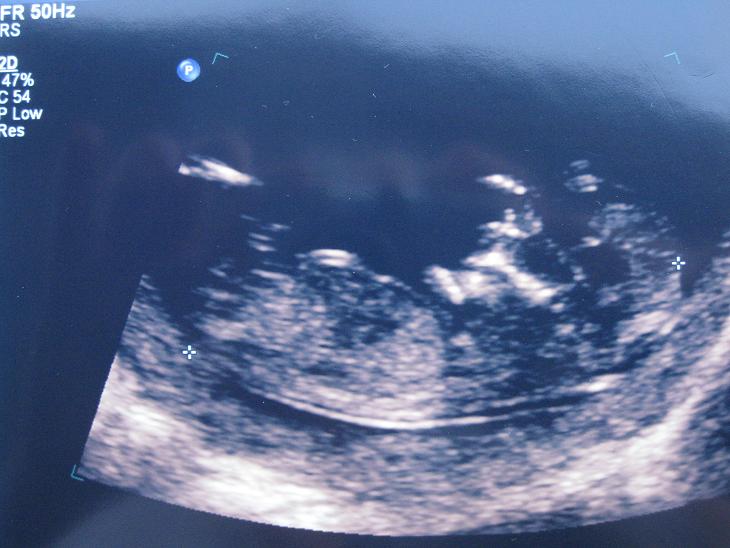

I was hoping that you may be able to share your thoughts on whether this little baby is a boy or girl.

Ultrasound photo:

This is a screen shot from the DVD where the sonographer gave her prediction (not sure how reliable as 2 minutes earlier she had guessed the other gender!):